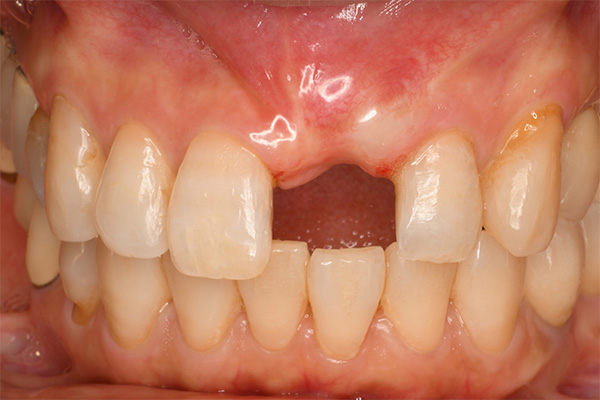

抜歯9ヶ月後(左)歯肉にヘコみができているので手術で歯肉を増大させる

装着時、歯肉は左右対称に近い感じになる